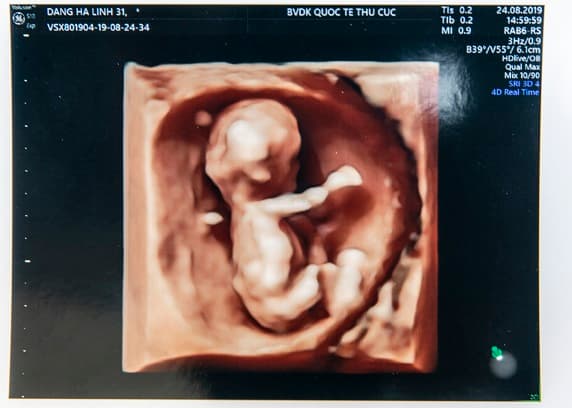

Siêu âm 5D không chỉ giúp mẹ quan sát được thai nhi một cách rõ nét, chi tiết nhất mà còn giúp bác sĩ có thể nhìn rõ cấu trúc bên trong của thai nhi như cấu trúc tim, não, sự chuyển động của chất lỏng… từ đó giúp bác sĩ có thể chẩn đoán, phát hiện các bất thường ở thai nhi ngay từ những tháng đầu tiên của thai kỳ.

Ưu điểm vượt trội của công nghệ siêu âm 5D so với các thế hệ siêu âm trước đó là giúp phát hiện sớm các dị tật về tim và não của thai nhi thông qua công nghệ chụp 9 mặt cắt tim, 6 hình ảnh hiển thị cho 3 mặt cắt ngang của não. Nhờ vậy, bác sĩ có thể chẩn đoán sớm và chính xác hơn các dị tật của thai nhi, ngay từ thời điểm thai 12 – 16 tuần.

Ngoài ra, siêu âm 5D còn hỗ trợ sàng lọc hầu hết các dị tật khác về hình thái của thai nhi như độ mờ da gáy, sứt môi, hở hàm ếch, phổi, thận…

Siêu âm 5D còn được tích hợp công nghệ bán tự động giúp các bác sĩ ước lượng chính xác hơn cân nặng và các chỉ số sinh trắc học của thai nhi như: Đường kính lưỡng đỉnh, chu vi đầu, chu vi bụng, chiều dài xương đùi…